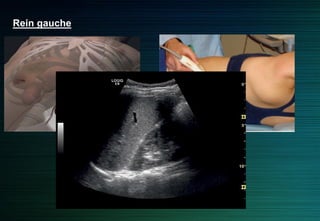

Rein gauche

Abord latéral ou postérolatéral

Rapport colique antérieur ou latéral

Rarement incidence antérolatérale

Rein